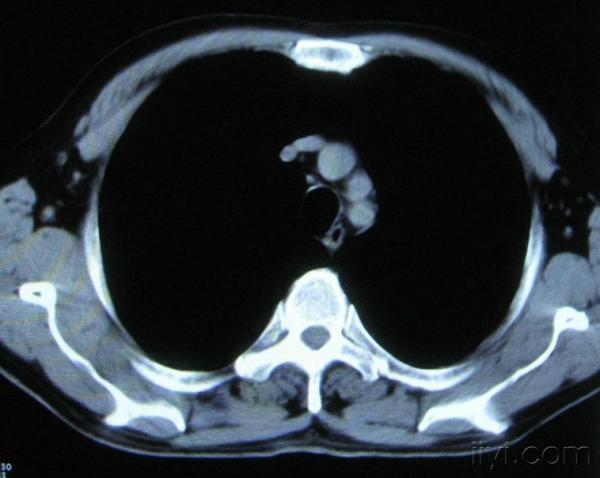

你指那个肯定是淋巴结,中央系坏死,这很常见,特别在双侧腹股沟会经常看到。这个双侧腋窝及纵隔见多发小淋巴结征。

根据位置考虑应该是淋巴结,密度不均,是因为肿大的淋巴结中心液化坏死